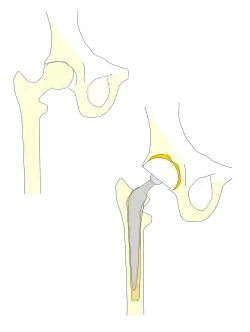

Prothèse totale de hanche

Une prothèse totale de hanche (PTH) est un dispositif articulaire interne qui vise à remplacer l'articulation de la hanche et lui permettre un fonctionnement quasi normal, en tout cas permettant la marche.